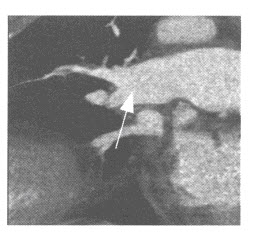

男性,65岁。咳嗽,憋气就诊。CT肺动脉造影如下图,可考虑为()

A、急性肺动脉栓塞

B、慢性肺动脉栓塞

C、肺动脉高压

D、肺动脉损伤

E、肺动脉狭窄

点击查看答案